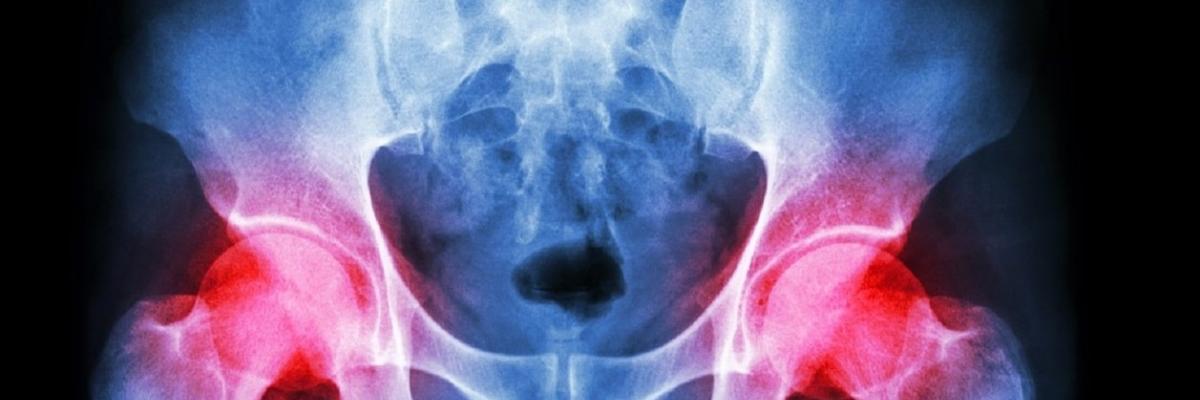

La Cadera, también llamada Articulación Coxofemoral, tiene como función mover los miembros inferiores hacia delante, atrás y a los lados; es decir, poder realizar movimientos como caminar, colocarse de cuclillas, doblar las piernas hacia arriba y aumentar la base de sustentación (abrir las piernas hacia los lados para evitar caerse).

Ahora bien, La Osteonecrosis de Cadera, consiste en la obstrucción de la circulación hacia el hueso de la cadera, específicamente al fémur, causando que el mismo no pueda seguir funcionando como debería. Cuando la Osteonecrosis lleva mucho tiempo afectando el hueso de la cadera se empiezan a dificultar aquellos movimientos que eran fáciles de realizar, causando así restricciones en las actividades de la vida diaria.